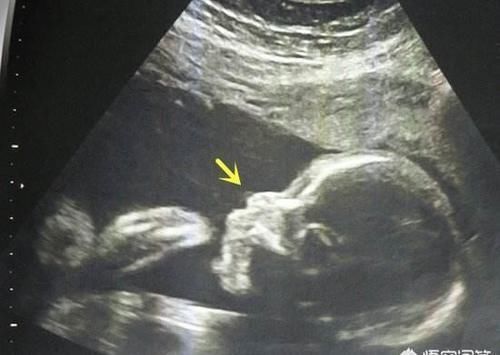

有研究表明,在没有鼻骨的胎宝宝当中,有25%左右的是21-三体综合征,就是我们常说的唐氏儿,还有约2.2%左右的是18-三体综合征,也属于一种染色体畸形,没有鼻骨的胎宝宝总体上出现染色体异常的几率是正常胎宝宝的21倍之多。那么,是不是说,如果查出来胎宝宝没有鼻骨,是不是这个胎宝宝就不可以要了呢?

当然不是。

在医学上,胎儿没有鼻骨其实只是一个超声“软指标”,也就是说,出现没有鼻骨的情况的胎宝宝可能是有问题的,但也可能是没有问题的,一般来说,12周以后胎宝宝的鼻骨就应该已经发育完全了,如果出现没有鼻骨的情况,孕妈妈是需要慎重对待的,有一部分没有鼻骨的胎宝宝还有别的方面的问题,那么畸形的几率会更加的大。